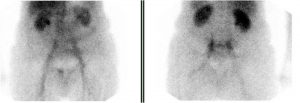

Fracture en H du sacrum

Femme de 78 ans

ATCD d’ostéoporose

Chute de sa hauteur

Douleur diffuse du bassin, bilan radiologique normal